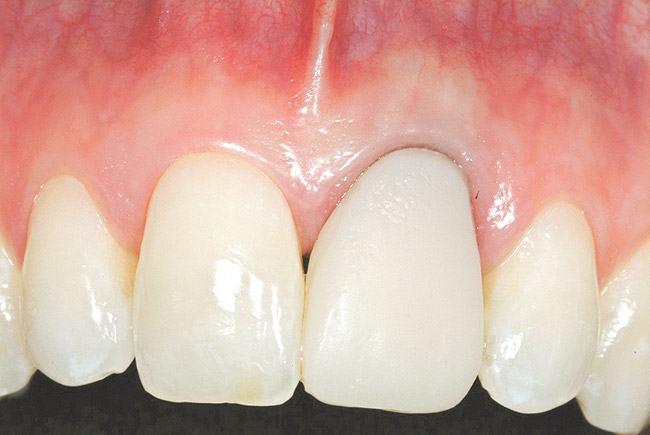

A 27-year-old non-smoking man presented for esthetic enhancement of the left central incisor, which had a pre-existing full-coverage restoration that required replacement (Figure 16). The patient had begun orthodontic treatment in the mandibular arch to correct a minor occlusal imbalance and required coronal repositioning and soft tissue grafting to correct gingival recession at the facial of the right canine, in addition to correction of the free gingival margin at the facial of the left central incisor, which was asymmetrical to the free gingival margin of tooth No. 8. Additionally, the facial gingival tissues were of a thin biotype, which at the facial surface of the left central incisor allowed for the darkened root surface to be visible through the tissue (Figure 16).

Figure 20 shows the completed view with the final restoration seated. Observe the balance of the facial heights of contour between the central incisors, and the presence of a thick-biotype, attached keratinized tissue.

Figure 16  Case Two Preoperative clinical view, maxillary left central incisor.

Figure 16

Figure 20  Case Two Case Two, complete view.

Figure 20